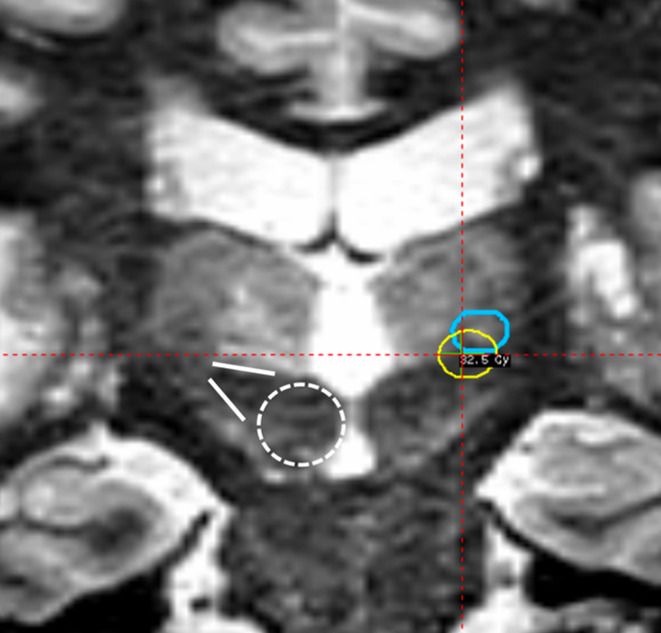

Enhanced visibility of relevant anatomy augments essential accuracy for treating functional indications